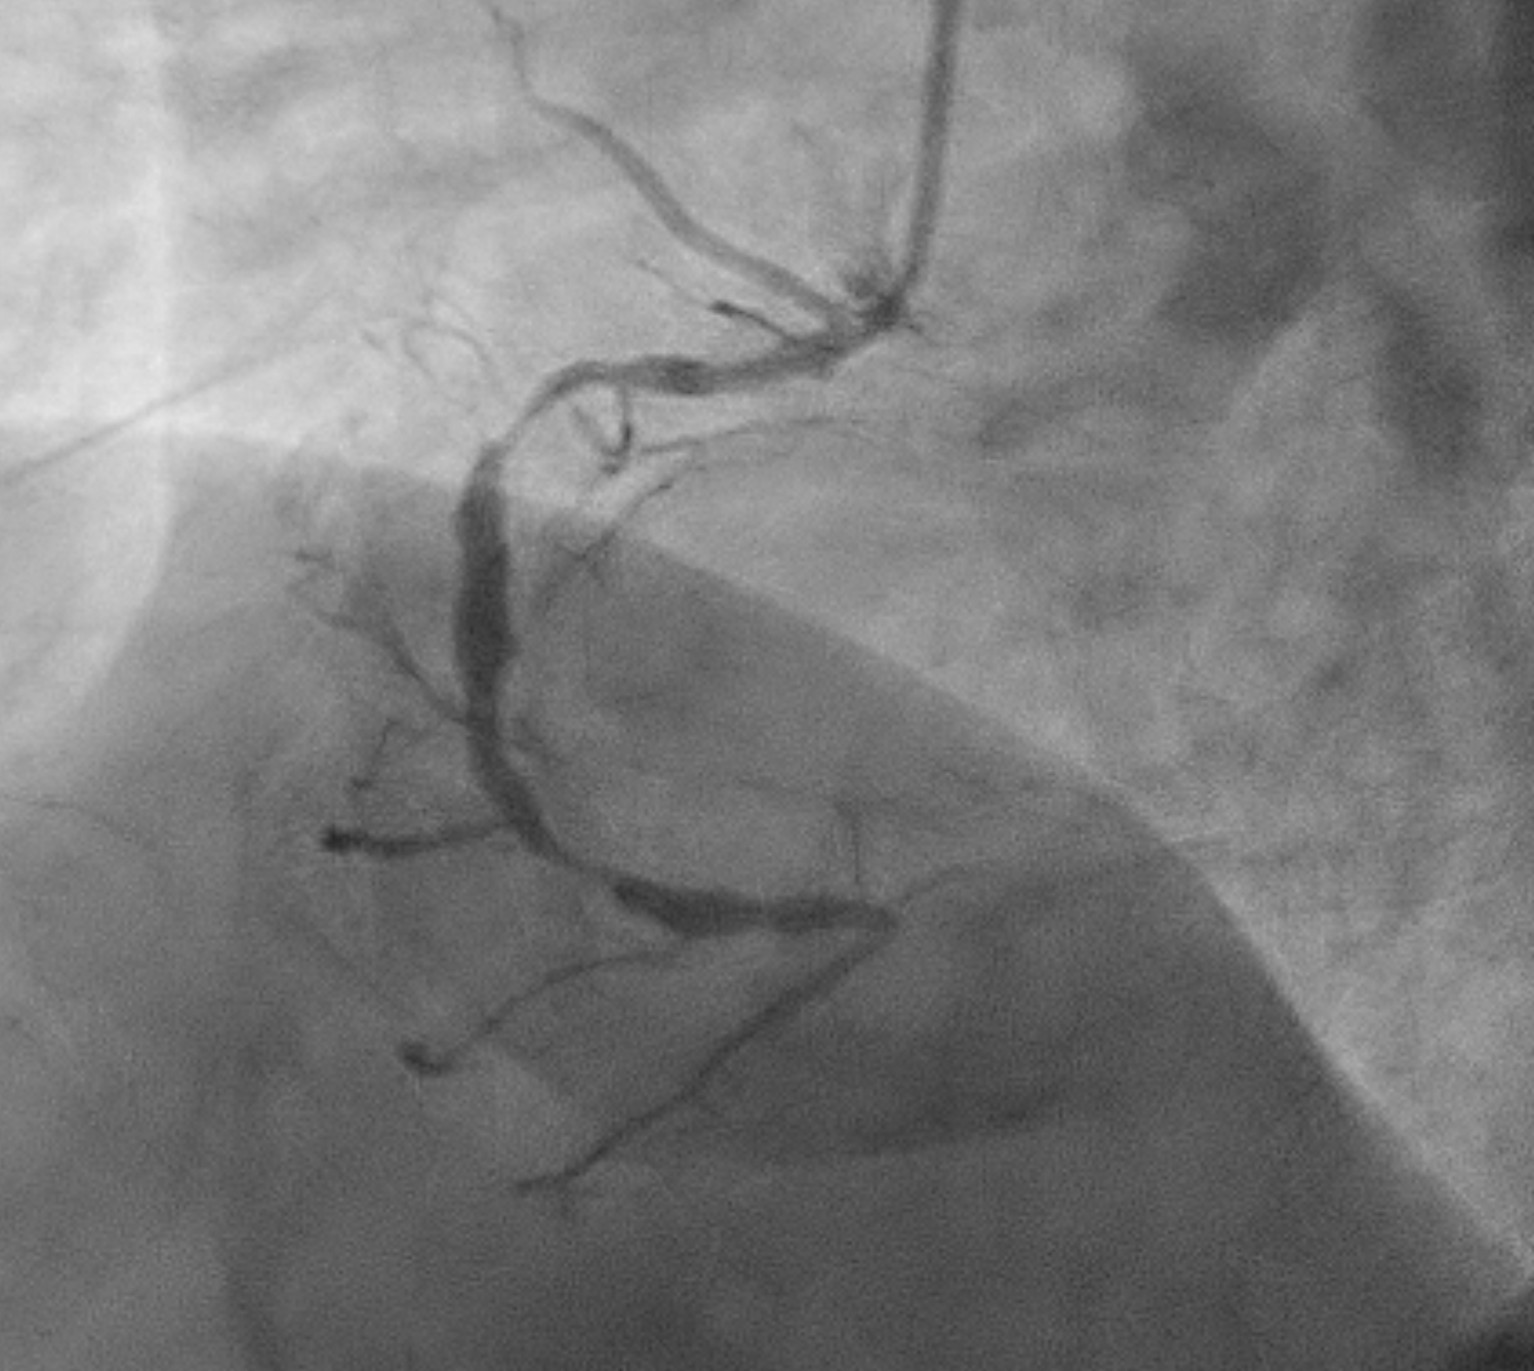

TRA diagnostic angiogram (pictures 1-3) showed mild distal LMS. Mild proximal-mid LAD stent <20% ISR and distal LAD 50% stenosis. Distal circumflex 50% stenosis. Proximal RCA 90% stenosis, distal 70% (segment 3) and then followed by total occlusion. Distal RCA received collaterals from LCA. Results discussed with patient who agreed for elective angioplasty to RCA.